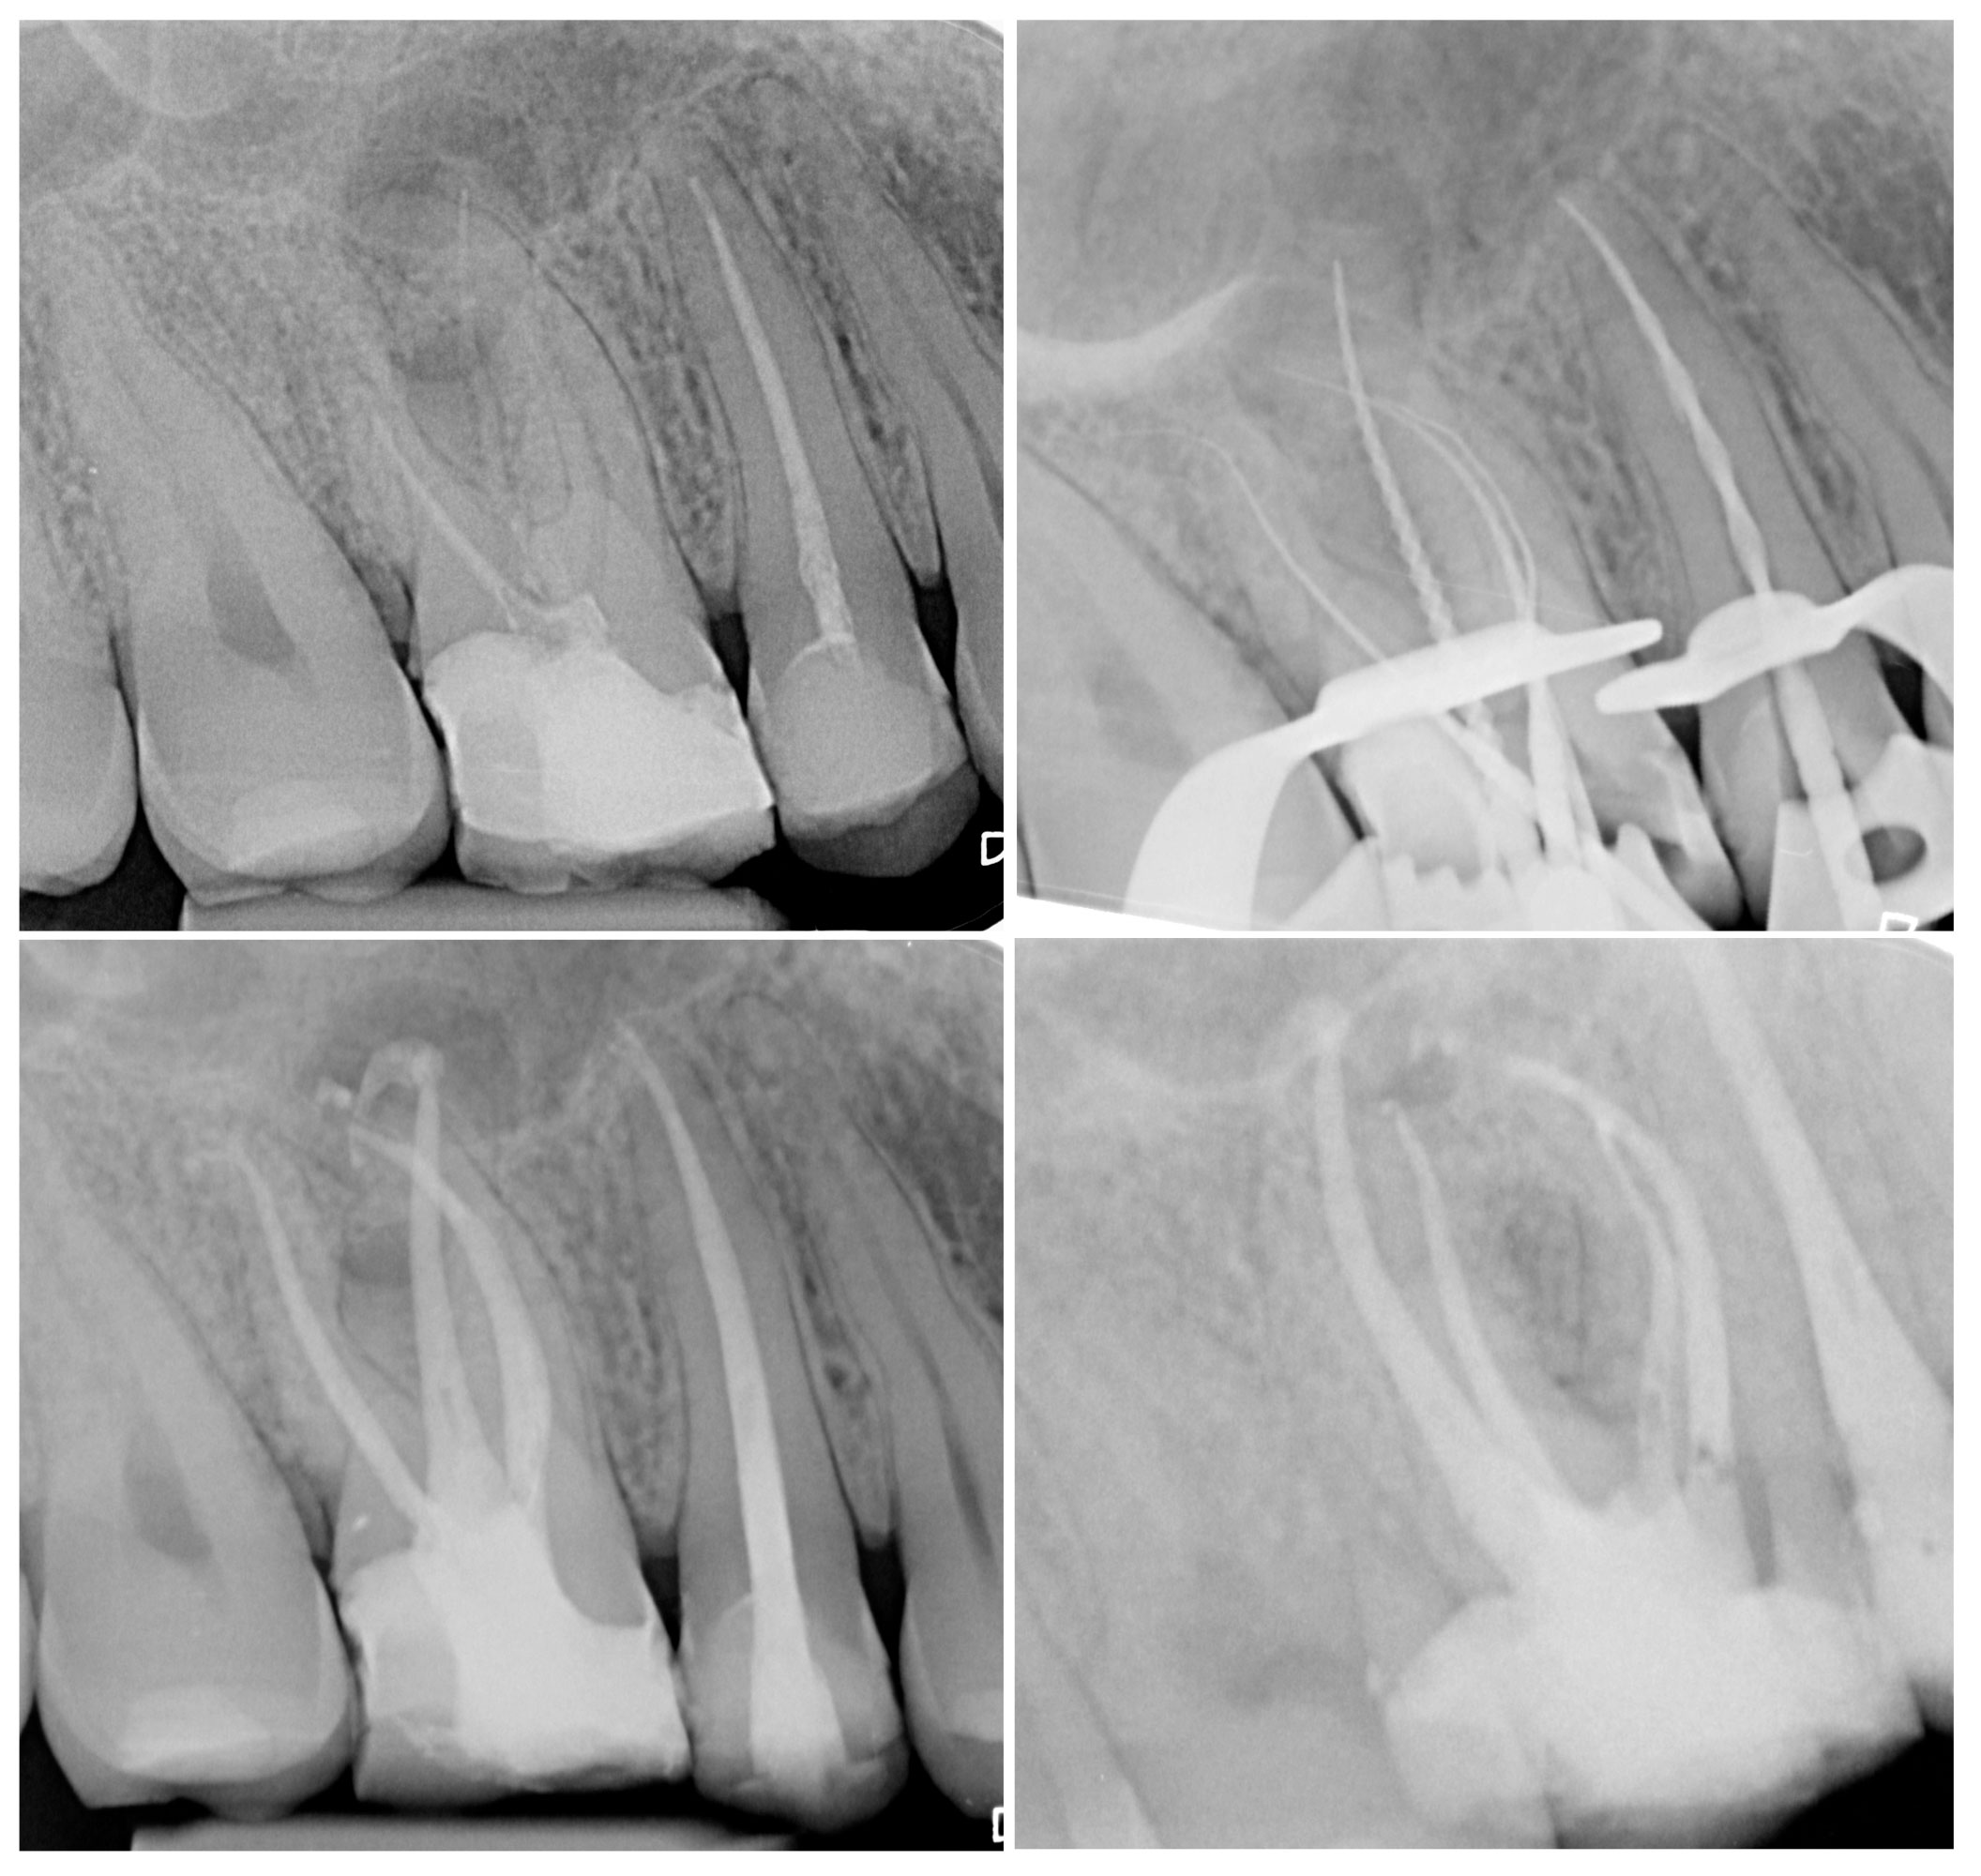

Dopo l’accesso alla camera pulpare e la localizzazione degli orifizi canalari la necessità di sondare i canali radicolari e creare un percorso di scorrimento (glide path) sicuro e prevedibile fino all’apice costituisce certamente una delle fasi più delicate del trattamento endodontico. Nella pratica clinica, oltre l’80% dei canali radicolari nei trattamenti primari può essere definito come “caso standard”, poiché questi canali presentano un glide path naturale che può essere percorso con successo fin dall’inizio e preparato agevolmente con una tecnica di strumentazione base.

Il restante 15-20% dei canali in trattamenti primari può essere definito come “caso complesso”, poiché questi canali possono presentare variazioni anatomiche che rendono la procedura di sondaggio la fase più delicata e complicata dell’intero trattamento.

Nei casi di ritrattamento invece, il primo ostacolo all’ottenimento della pervietà del lume canalare, è rappresentato dalla necessità di rimuovere il materiale da otturazione canalare presente; questa fase può essere oggi facilmente e rapidamente superata attraverso il corretto utilizzo di strumenti utilizzati con movimento reciprocante. Molto spesso, nei ritrattamenti la problematica più complessa è rappresentata dalla presenza di gradini o canali bloccati apicalmente dal vecchio materiale da otturazione canalare.

Verranno analizzati diversi possibili scenari clinici, considerando dapprima i casi in cui il glide path è presente sin dall’inizio della terapia; successivamente verrà analizzato perché, in alcuni casi, ci siano difficoltà nella negoziazione causate da impedimenti che possono essere coronali o apicali e verrà illustrato come affrontare clinicamente queste situazioni. In questi casi, sarà anche descritto l’uso di strumenti reciprocanti di piccole dimensioni nel sondaggio di canali particolarmente complessi. Verrano descritte tecniche ibride in cui utilizzare alternare la tipologia di metallo (austenitica e martensitica) e la taglia dello strumento nei casi clinici con curvature radicolari estreme ed infine la strategia per approcciare casi che richiedono una preparazione minimamente invasiva al fine di preservare la dentina pericervicale. Verrano infine date le indicazioni alla risoluzione chirurgica di problematiche endodontiche ed eventuali possibilità della tecnica del reimpianto intenzionale.